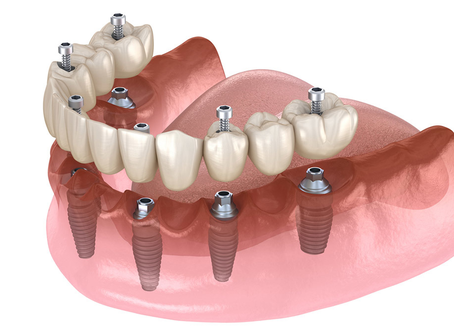

- Cirugía de injertos óseos: para recuperar volumen óseo perdido antes de implantes.

La planificación de una cirugía dental moderna inicia con un diagnóstico integral, que incluye examen clínico, radiografías digitales y, en algunos casos, tomografía 3D. Estas herramientas permiten visualizar la estructura ósea, la posición de los dientes y la proximidad a nervios o senos maxilares, lo que minimiza riesgos y optimiza la intervención.